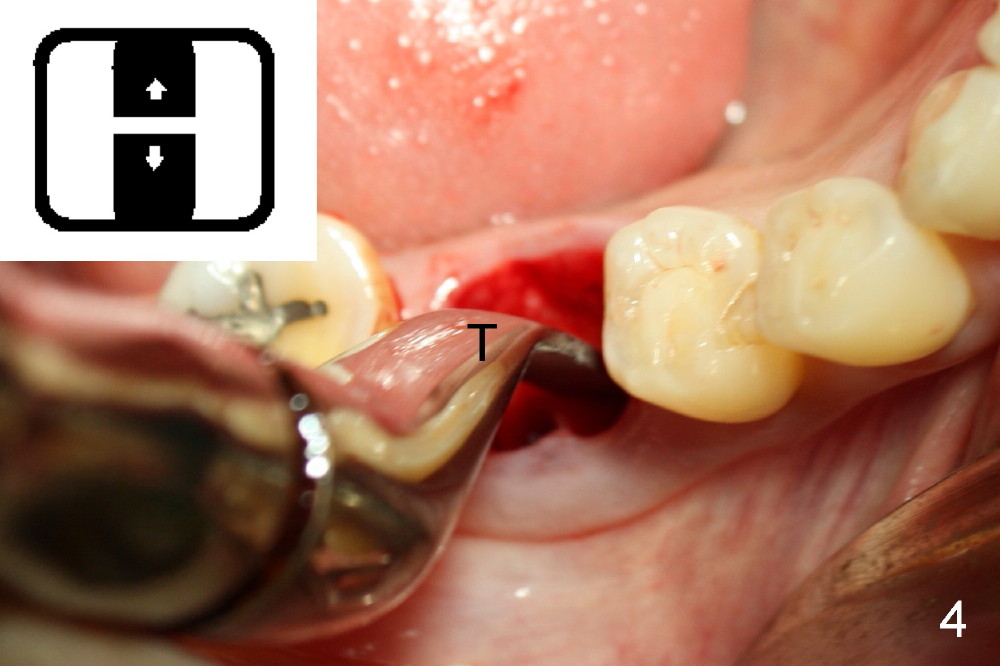

A sixty-year-old lady fractured the crown of the lower right first molar (Fig.1). The residual roots were sectioned (Fig.2 between arrowheads) and removed. The septum (Fig.3 *) is round on the top between mesial and distal sockets (1,2). Thin osteotomes (bone scalpel, bone blade; Fig.4: T) were used to section the septum mesiodistally. Fig.5 shows the sectioned septum, which makes it easy to insert round tapered osteotomes (Fig.5 inset green; Fig.6 R) without slipping either into the mesial or distal socket.